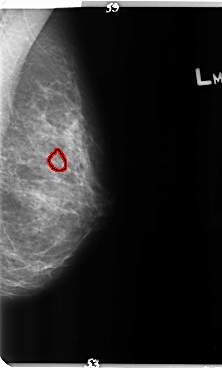

B_3150_1.LEFT_MLO

LEFT_MLO LINES 4784 PIXELS_PER_LINE 2880 BITS_PER_PIXEL 12 RESOLUTION 50 OVERLAY

FILE: B_3150_1.LEFT_MLO.OVERLAY

TOTAL_ABNORMALITIES 1

ABNORMALITY 1

LESION_TYPE CALCIFICATION TYPE PLEOMORPHIC DISTRIBUTION CLUSTERED

ASSESSMENT 4

SUBTLETY 3

PATHOLOGY BENIGN

TOTAL_OUTLINES 1

BOUNDARY